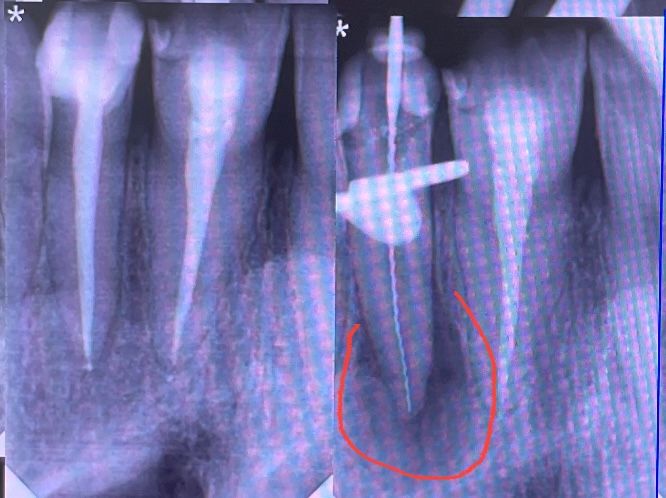

Я так намучалась с этой кистой. Обнаружили её 5 лет назад, записалась я в самую, как мне показалось, лучшую клинику , каждые две недели ходила на прием, через каналы закладывали лекарство, промывали растворами, спустя пару месяц сказали идем к лучшему результату, далее услышала «всё вылечили». Я даже не догадалась перепроверить. Как оказалось не вылечили, спустя 4 года (то есть год назад заболел этот зуб, несильно, но ощущения были странные) бегом ко врачу, рентген и каково было удивление, что киста на месте, переодонтит процветает. Была у 3 врачей, два сказали удалять через десну корень, третий вообще серьезной проблемы не заметил. Хороша не пошла к хирургу удалять, а решила всё таки найти грамотного специалиста. Нашла, да снова муторное лечение пару месяцев , не дешевое это «удовольствие» , но результат замечательный. Фото прилагаю (первый рентген обведено красным и спустя 6 месяцев)